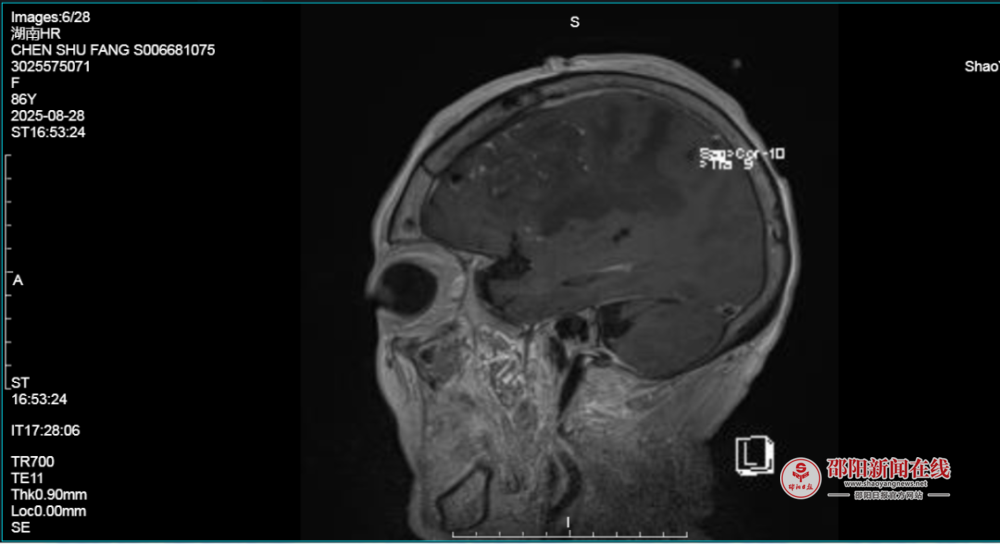

8月27日,由蒋开源主任带领的神经肿瘤团队为陈奶奶进行开颅手术。手术进行顺利,颅内肿瘤完全切除。患者术后转至神经重症监护室,在一系列高精尖的预防性监护措施下,大大降低了并发症的发生率,提高了患者的治愈率。

康复护理团队也立即按照术前规划,从运动指导、排痰、雾化吸入等早期训练,到肢体功能训练,再到离床短距离步行训练,开始了循序渐进、有条不紊的康复。术后12小时,陈奶奶便转入普通病房,开始喝稀粥;24小时拔管后开始下床,开始了早期的神经功能恢复。